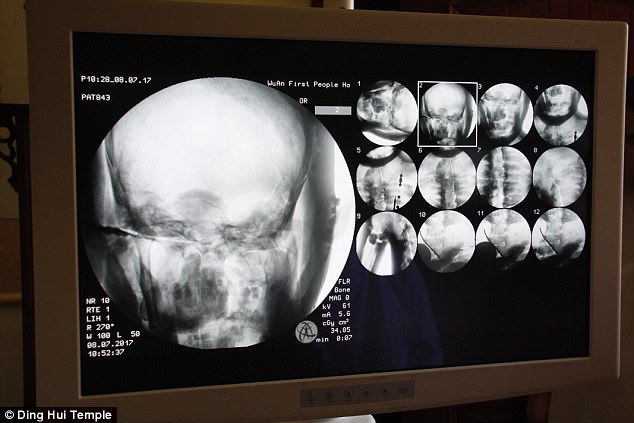

În urma tomografiilor computerizate, preoţii, medicii şi ceilalţi martori au fost uimiţi când au observat că mumia maestrului Ci Xian avea întregul creier şi structura osoasă. ,,Oasele sale sunt la fel de sănătoase precum cele ale unei persoane normale. Partea superioară a mandibulei, dinţii superiori, coastele, coloana şi toate încheieturile sunt la locul lor. Este incredibil,” a declarat dr. Wu Yongqing.